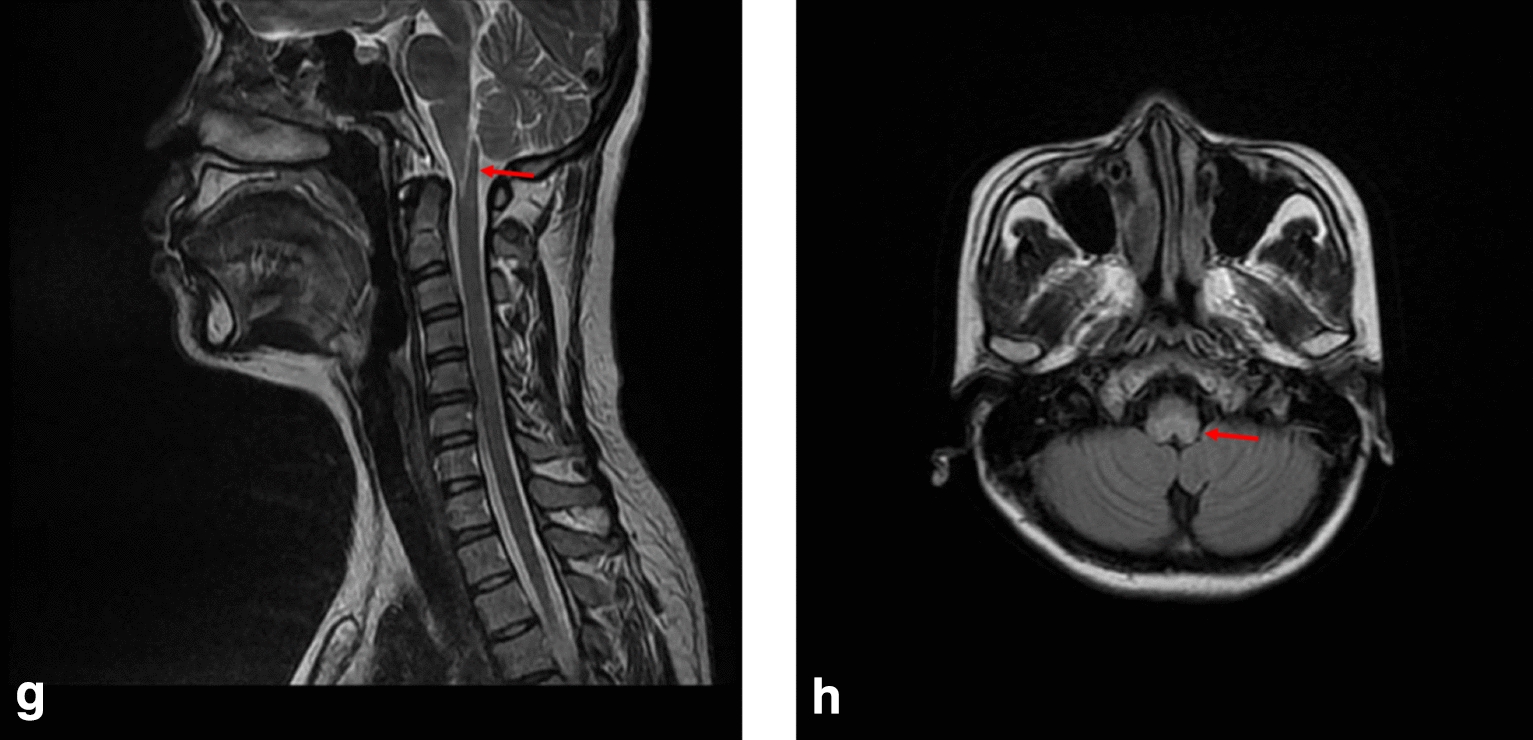

Fig. 4.

MRI T2 sequence of case 4 showing hyperintense in medulla oblongata (highlighted by arrows) in the g sagittal planes and h transverse planes